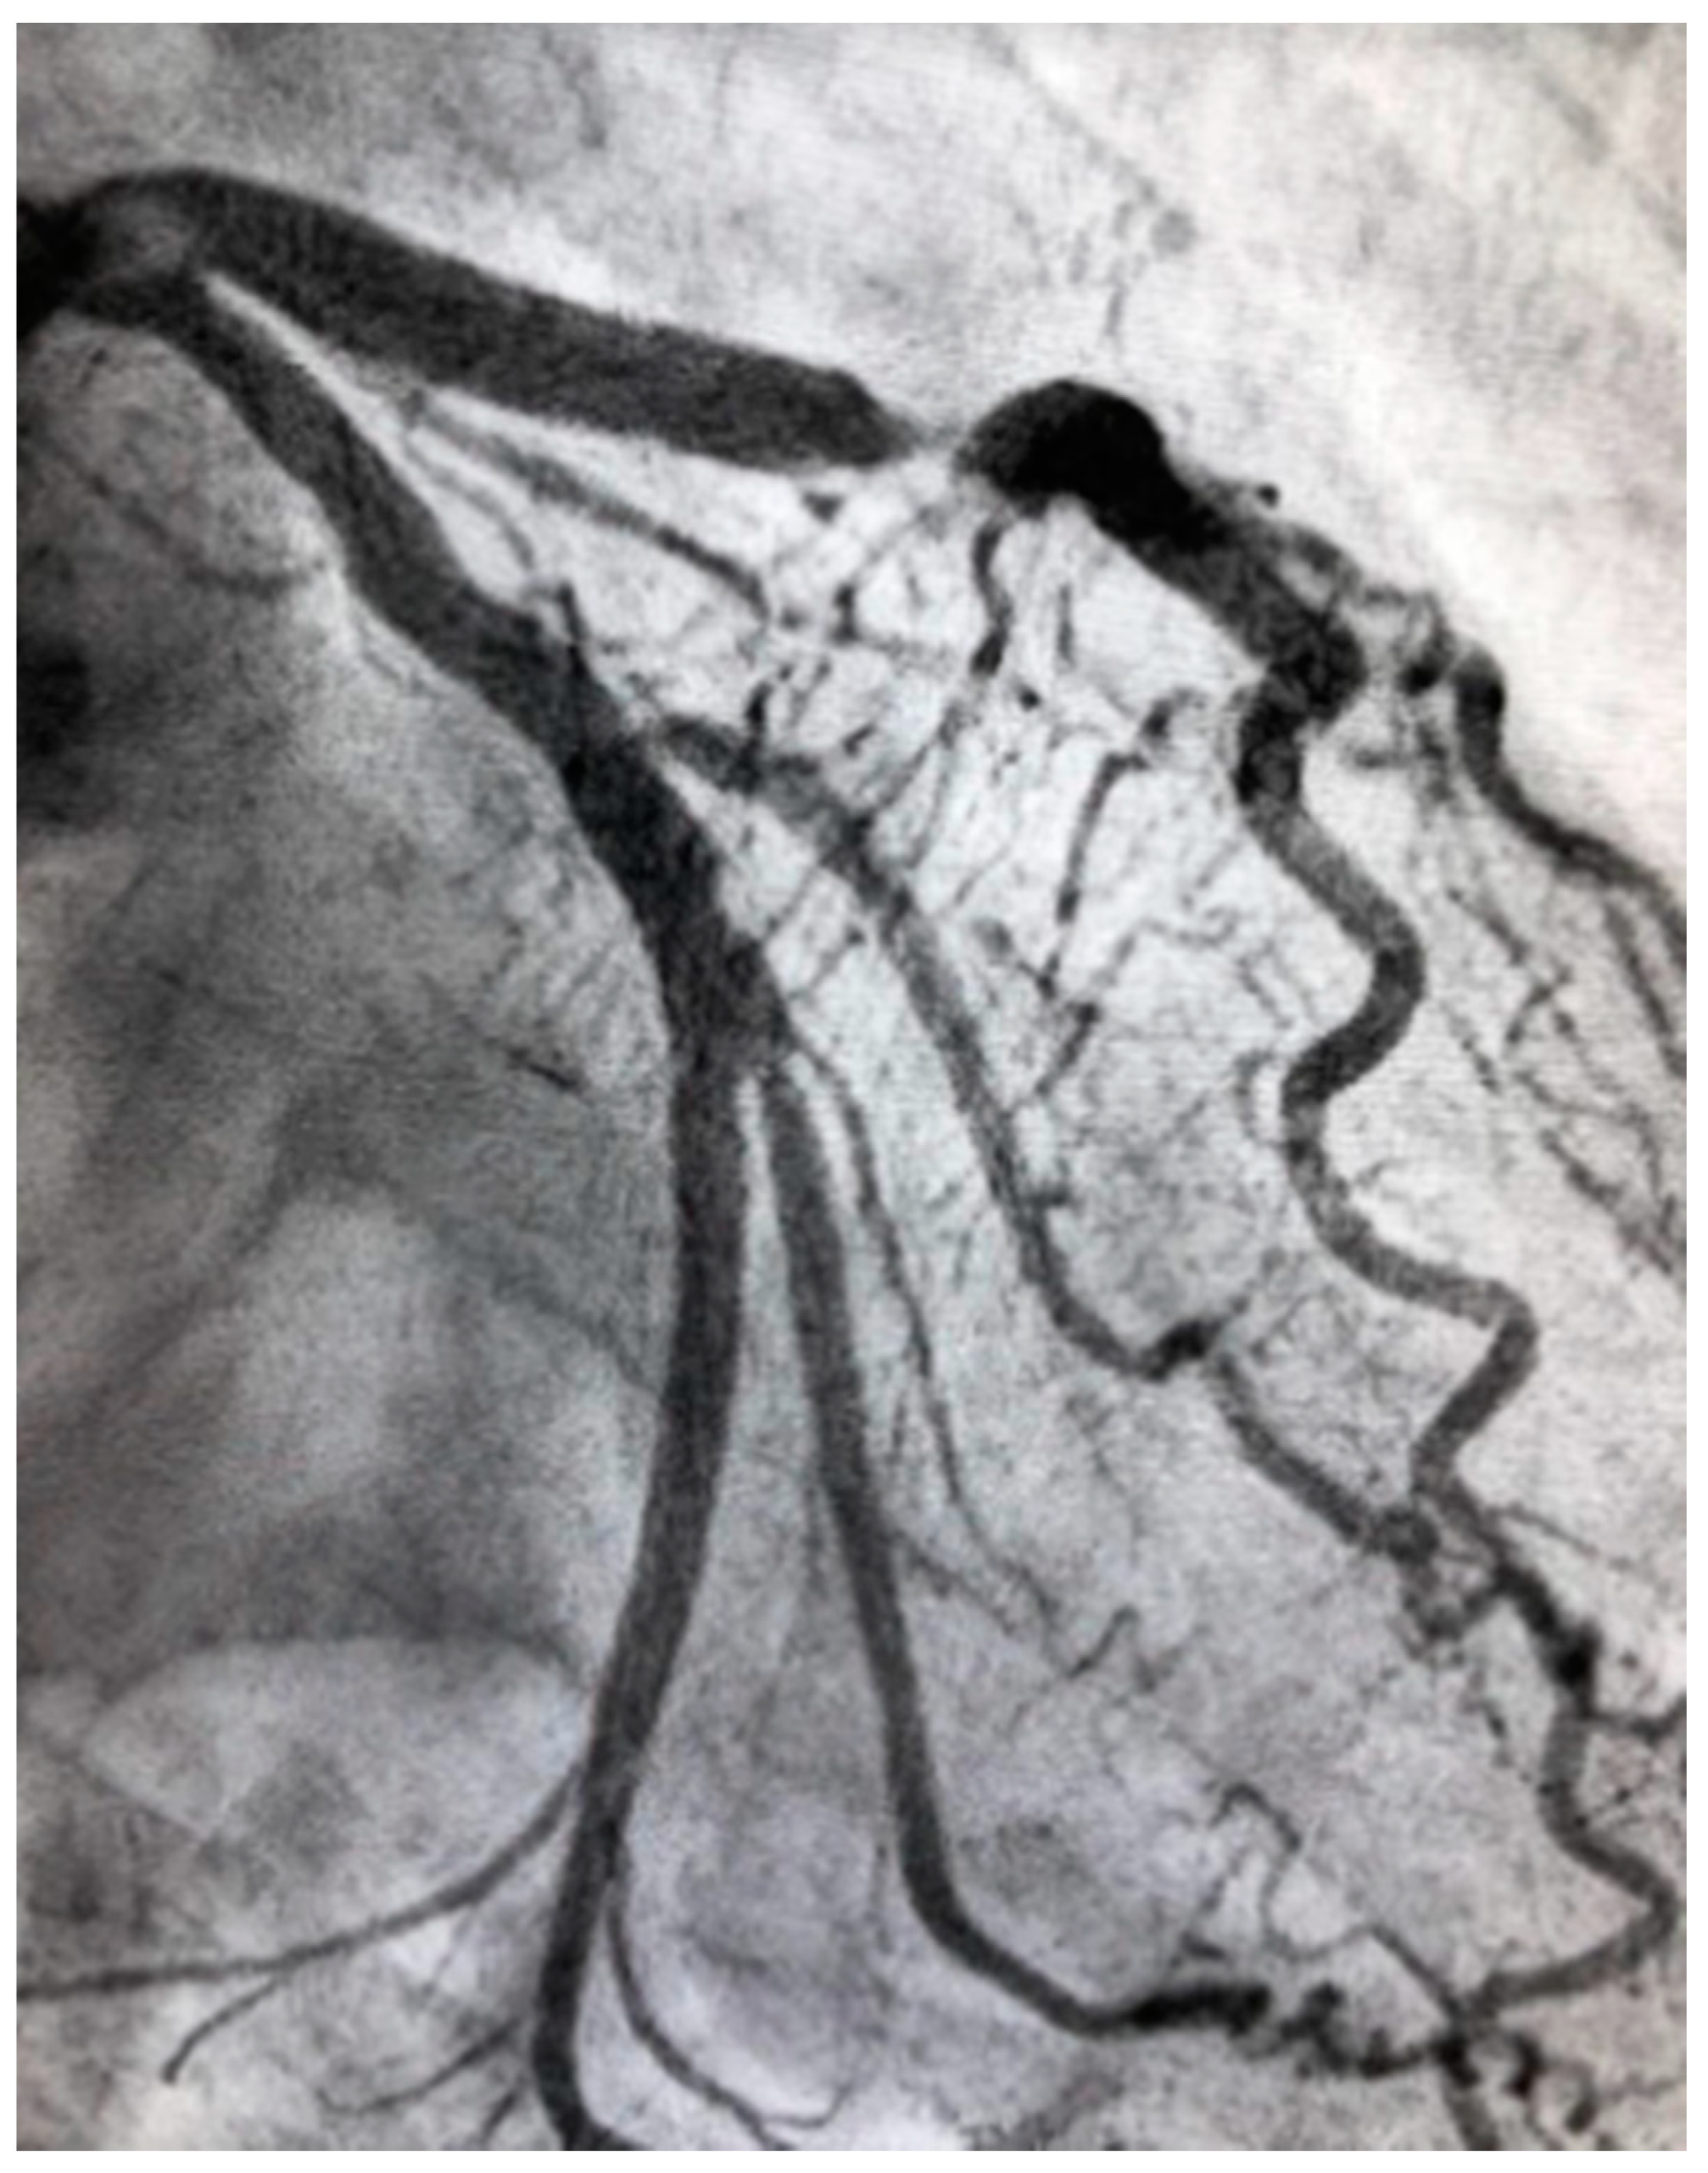

4.4. Spontaneous Coronary Artery Dissection

- Hayes, S.N.; Kim, E.S.; Saw, J.; Adlam, D.; Arslanian-Engoren, C.; Economy, K.E.; Ganesh, S.K.; Gulati, R.; Lindsay, M.E.; Mieres, J.H.; et al. Spontaneous Coronary Artery Dissection: Current State of the Science: A Scientific Statement From the American Heart Association. Circulation 2018, 137, e523–e557. [Google Scholar] [CrossRef] [PubMed] [Green Version]